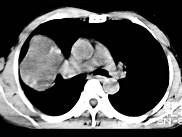

根据所提供的图像,选择最可能的诊断 ( )A、机化性肺炎B、局限性不张C、胸膜间皮瘤D、球形肺炎E、肺内软骨肉瘤

问题 根据所提供的图像,选择最可能的诊断 ( )

选项 A、机化性肺炎 B、局限性不张 C、胸膜间皮瘤 D、球形肺炎 E、肺内软骨肉瘤

答案 E